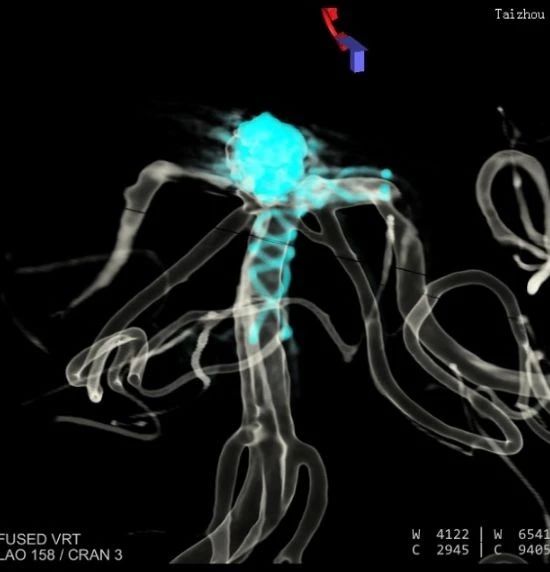

術(shù)中影像重建顯示的不同角度的動脈瘤,看起來很漂亮哦

術(shù)后彈簧圈和顱內(nèi)支架的影像重建。圓球形的是彈簧圈,麻花樣的就是顱內(nèi)支架。